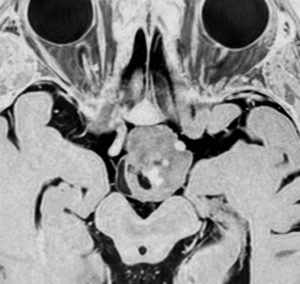

• 視神経や中脳のものでは,手術をする前にはCISSというMRI画像が必要です

• なぜかというと,腫瘍がどこから発生したかを詳細に読み取ることで,手術の作戦が決定されることです

• 視神経交叉から出たのならば,全摘出すれば全盲を覚悟しないとなりません

• 片方の視神経から出て巨大になったものなら,全部とっても片方の失明だけですみます

• 視床下部から出たもののごく一部は全摘出できることがあります

• でも両側の視床下部に明らかに浸潤するものを全摘出すると,ひどい視床下部損傷で通常の生活ができなくなることがあります

• 視索が大きく膨れる腫瘍を摘出すれば,同名半盲になりますし,このタイプは取りきれるものではありません